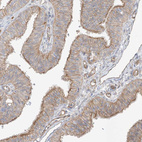

Immunohistochemical staining of human cerebral cortex shows strong cytoplasmic positivity in neurons.